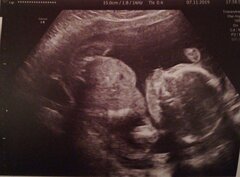

Selon Els Van Hoof (CD&V), ces propositions de loi « brisent le nécessaire équilibre à maintenir entre les intérêts de la femme et ceux de l'enfant à naître ». Citant le dernier rapport de la commission d'évaluation de l'avortement aux Pays-Bas, qui indique que 472 femmes belges ont été avorter dans ce pays, la députée note qu'on ne sait pas à quel stade de la grossesse ces femmes se trouvaient (possiblement aussi avant 12 semaines), ni les raisons qui les ont amenées à avorter aux Pays-Bas. En commission, Els Van Hoof a également osé décrire les méthodes d'avortement pendant le deuxième trimestre de grossesse, plus lourdes physiquement et psychologiquement, et plus risquées pour la santé de la femme : à savoir le déclenchement de l'accouchement (précédé de l'euthanasie du foetus ou suivi de son décès dès qu'il quitte le ventre de sa mère), et de celle de la dilatation du col de l'utérus avec extraction du foetus, souvent par morceaux.

La députée Valérie Van Peel (NV-A) a souligné la gravité des enjeux éthiques de la proposition de loi : « Un débat éthique demande d'examiner le sujet en prenant en considération toutes les parties concernées : la femme, l'entourage de la femme, le foetus, les médecins. » Pour la députée, il faut que la société réalise ce que signifie un avortement à 18 semaines.  Quant au délai obligatoire de réflexion qu'une majorité veut limiter à 48h, elle a rappelé que « ce délai de 6 jours vise à protéger les plus faibles : des femmes qui sont sous pression, qui ont besoin de temps, parfois pour changer d'avis et garder l'enfant. »